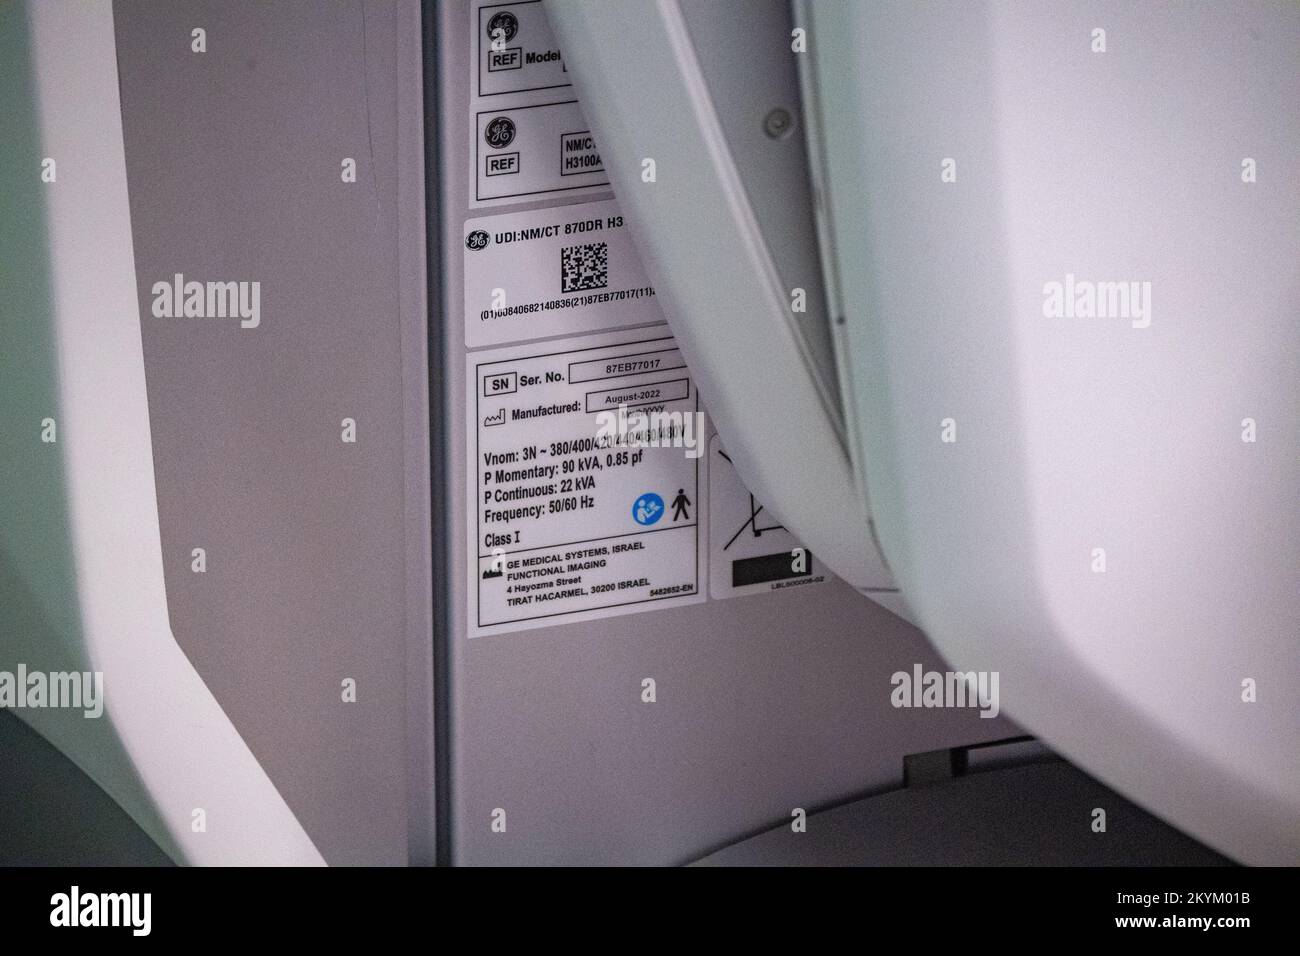

RM2KYM014–01 décembre 2022, Mecklembourg-Poméranie occidentale, Greifswald: Un panneau avec les mots «Telemedically Integrated, German-Polish Pediatric cancer Center dans l'Eurorégion Pomerania» est accroché derrière un dispositif NM/CT 870 DR de General Electric Medical Systems, Israël dans les salles de la clinique pédiatrique du centre médical de l'université Greifswald. Ce système SPECT/CT permet des examens médicaux nucléaires encore plus précis. Ceci est nécessaire pour les options de traitement spéciales telles que la thérapie par radio-isotope. La tomodensitométrie (CT) utilise un grand nombre d'images radiologiques pour calculer les images numériques. Une acquisition SPECT, sur t

RM2KYKWRC–01 décembre 2022, Mecklembourg-Poméranie occidentale, Greifswald: Une unité NM/CT 870 DR de General Electric Medical Systems, Israël est sur le point d'être remise dans les salles de la clinique pédiatrique du centre médical de l'université Greifswald. Ce système SPECT/CT permet des examens médicaux nucléaires encore plus précis. Ceci est nécessaire pour les options de traitement spéciales telles que la thérapie par radio-isotope. La tomodensitométrie (CT) utilise un grand nombre d'images radiologiques pour calculer les images numériques. Une acquisition SPECT, en revanche, utilise une caméra gamma pour rendre visible le faible rayonnement des médicaments radioactifs. Dans cette wa

RM2KYM017–01 décembre 2022, Mecklembourg-Poméranie occidentale, Greifswald: Un dispositif NM/CT 870 DR de General Electric Medical Systems, Israël est sur le point d'être remis dans les salles de la clinique pédiatrique du centre médical de l'université de Greifswald. Ce système SPECT/CT permet des examens médicaux nucléaires encore plus précis. Ceci est nécessaire pour les options de traitement spéciales telles que la thérapie par radio-isotope. La tomodensitométrie (CT) utilise un grand nombre d'images radiologiques pour calculer les images numériques. Une acquisition SPECT, en revanche, utilise une caméra gamma pour rendre visible le faible rayonnement des médicaments radioactifs. Dans cette

RM2KYM01N–01 décembre 2022, Mecklembourg-Poméranie occidentale, Greifswald: Une unité NM/CT 870 DR de General Electric Medical Systems, Israël est sur le point d'être remise dans les salles de la clinique pédiatrique du centre médical de l'université Greifswald. Ce système SPECT/CT permet des examens médicaux nucléaires encore plus précis. Ceci est nécessaire pour les options de traitement spéciales telles que la thérapie par radio-isotope. La tomodensitométrie (CT) utilise un grand nombre d'images radiologiques pour calculer les images numériques. Une acquisition SPECT, en revanche, utilise une caméra gamma pour rendre visible le faible rayonnement des médicaments radioactifs. Dans cette wa

RM2KYM018–01 décembre 2022, Mecklembourg-Poméranie occidentale, Greifswald: Un panneau avec les mots «Telemedically Integrated, German-Polish Pediatric cancer Center dans l'Eurorégion Pomerania» est accroché derrière un dispositif NM/CT 870 DR de General Electric Medical Systems, Israël dans les salles de la clinique pédiatrique du centre médical de l'université Greifswald. Ce système SPECT/CT permet des examens médicaux nucléaires encore plus précis. Ceci est nécessaire pour les options de traitement spéciales telles que la thérapie par radio-isotope. La tomodensitométrie (CT) utilise un grand nombre d'images radiologiques pour calculer les images numériques. Une acquisition SPECT, sur t

RM2KYKWW0–01 décembre 2022, Mecklembourg-Poméranie occidentale, Greifswald: Une unité NM/CT 870 DR de General Electric Medical Systems, Israël est sur le point d'être remise dans les salles de la clinique pédiatrique du centre médical de l'université Greifswald. Ce système SPECT/CT permet des examens médicaux nucléaires encore plus précis. Ceci est nécessaire pour les options de traitement spéciales telles que la thérapie par radio-isotope. La tomodensitométrie (CT) utilise un grand nombre d'images radiologiques pour calculer les images numériques. Une acquisition SPECT, en revanche, utilise une caméra gamma pour rendre visible le faible rayonnement des médicaments radioactifs. Dans cette wa

RM2KYKWT3–01 décembre 2022, Mecklembourg-Poméranie occidentale, Greifswald: Une unité NM/CT 870 DR de General Electric Medical Systems, Israël est sur le point d'être remise dans les salles de la clinique pédiatrique du centre médical de l'université Greifswald. Ce système SPECT/CT permet des examens médicaux nucléaires encore plus précis. Ceci est nécessaire pour les options de traitement spéciales telles que la thérapie par radio-isotope. La tomodensitométrie (CT) utilise un grand nombre d'images radiologiques pour calculer les images numériques. Une acquisition SPECT, en revanche, utilise une caméra gamma pour rendre visible le faible rayonnement des médicaments radioactifs. Dans cette wa

RM2KYM01B–01 décembre 2022, Mecklembourg-Poméranie occidentale, Greifswald: Un dispositif NM/CT 870 DR de General Electric Medical Systems, Israël est sur le point d'être remis dans les salles de la clinique pédiatrique du centre médical de l'université de Greifswald. Ce système SPECT/CT permet des examens médicaux nucléaires encore plus précis. Ceci est nécessaire pour les options de traitement spéciales telles que la thérapie par radio-isotope. La tomodensitométrie (CT) utilise un grand nombre d'images radiologiques pour calculer les images numériques. Une acquisition SPECT, en revanche, utilise une caméra gamma pour rendre visible le faible rayonnement des médicaments radioactifs. Dans cette

RM2KYM01C–01 décembre 2022, Mecklembourg-Poméranie occidentale, Greifswald: Une unité NM/CT 870 DR de General Electric Medical Systems, Israël est sur le point d'être remise dans les salles de la clinique pédiatrique du centre médical de l'université Greifswald. Ce système SPECT/CT permet des examens médicaux nucléaires encore plus précis. Ceci est nécessaire pour les options de traitement spéciales telles que la thérapie par radio-isotope. La tomodensitométrie (CT) utilise un grand nombre d'images radiologiques pour calculer les images numériques. Une acquisition SPECT, en revanche, utilise une caméra gamma pour rendre visible le faible rayonnement des médicaments radioactifs. Dans cette wa

RM2KYKWRP–01 décembre 2022, Mecklembourg-Poméranie occidentale, Greifswald: Un dispositif NM/CT 870 DR de General Electric Medical Systems, Israël est sur le point d'être remis dans les salles de la clinique pédiatrique du centre médical de l'université de Greifswald. Ce système SPECT/CT permet des examens médicaux nucléaires encore plus précis. Ceci est nécessaire pour les options de traitement spéciales telles que la thérapie par radio-isotope. La tomodensitométrie (CT) utilise un grand nombre d'images radiologiques pour calculer les images numériques. Une acquisition SPECT, en revanche, utilise une caméra gamma pour rendre visible le faible rayonnement des médicaments radioactifs. Dans cette

RM2KYM01E–01 décembre 2022, Mecklembourg-Poméranie occidentale, Greifswald: Une unité NM/CT 870 DR de General Electric Medical Systems, Israël est sur le point d'être remise dans les salles de la clinique pédiatrique du centre médical de l'université Greifswald. Ce système SPECT/CT permet des examens médicaux nucléaires encore plus précis. Ceci est nécessaire pour les options de traitement spéciales telles que la thérapie par radio-isotope. La tomodensitométrie (CT) utilise un grand nombre d'images radiologiques pour calculer les images numériques. Une acquisition SPECT, en revanche, utilise une caméra gamma pour rendre visible le faible rayonnement des médicaments radioactifs. Dans cette wa